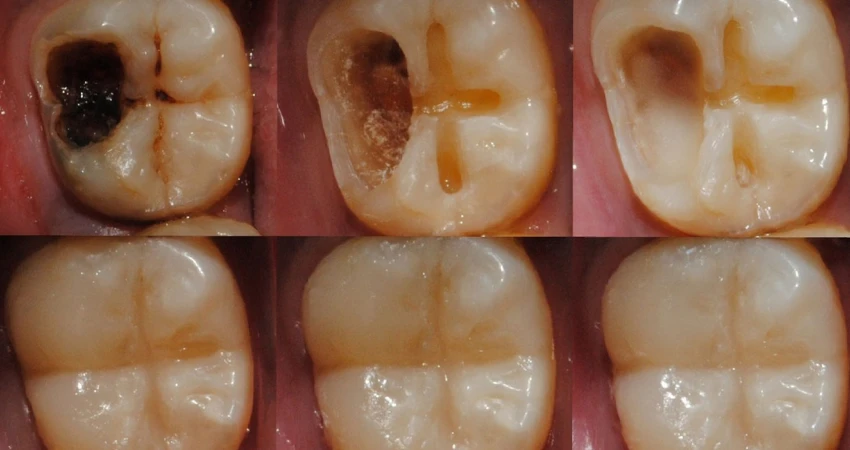

يختلف علاج تسوس الأسنان العميق عن التسوس السطحي؛ إذ يتطلب تدخلاً أكثر دقة للحفاظ على السن ومنع فقدانه نهائيًا. يبدأ الطبيب عادةً بإزالة الجزء المتسوس من السن باستخدام أدوات خاصة، ثم تنظيف التجويف بعمق للتخلص من البكتيريا وبقايا الطعام التي تسبب الألم والالتهاب.

بعد ذلك يتم حشو السن بحشوة تجميلية أو معدنية مناسبة لإعادة بنية السن الطبيعية وتقوية جدرانه، وفي حال وصول التسوس إلى عصب السن يتم اللجوء إلى علاج جذور الأسنان (سحب العصب) لتنظيف القنوات العصبية وتعقيمها ثم حشوها بإحكام.

قد يوصي الطبيب بتركيب تاج أو تلبيسة للسن المتضرر لحمايته من الكسر وتحسين مظهره ووظيفته، خاصة في الحالات المتقدمة من تسوس الأسنان العميق.